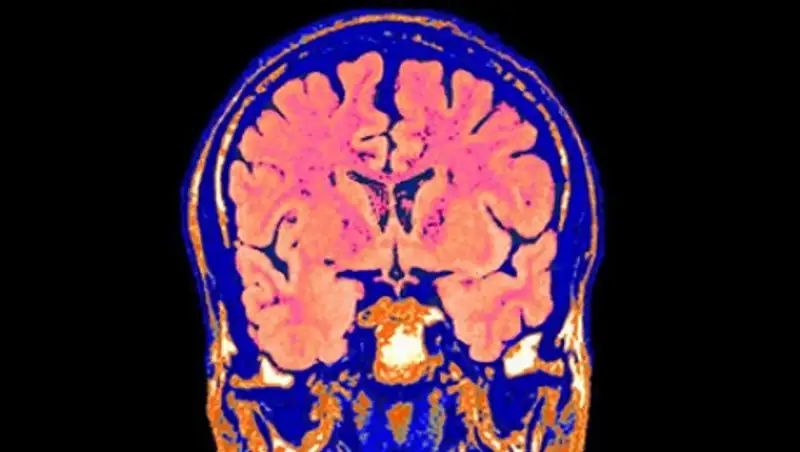

Результаты нового исследования демонстрируют, что определенные функции мозга могут быть восстановлены даже через несколько часов после смерти.

Американские ученые создали систему BrainEx, которая способна восстанавливать кровообращение и некоторые функции мозга свиньи, мертвой в течение нескольких часов. Однако исследователи не смогли восстановить восприятие и другие высшие нервные процессы, передает Lenta.ru.

Известно, что мозг животных чувствителен к пониженным концентрациям кислорода. Серьезные нарушения в кровотоке приводят к быстрому истощению запасов энергии, необходимой для жизнедеятельности нейронов и необратимым повреждениям нервных тканей. Однако некоторые специалисты сомневались, что это разрушительное воздействие является неизбежным в течение относительно коротких периодов гипоксии. Результаты нового исследования демонстрируют, что определенные функции мозга могут быть восстановлены даже через несколько часов после смерти.